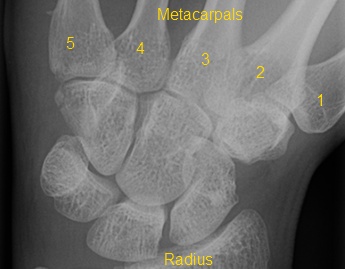

A baseball player has immediate pain on the ulnar aspect of his palm after hitting a line drive. What is the diagnosis?